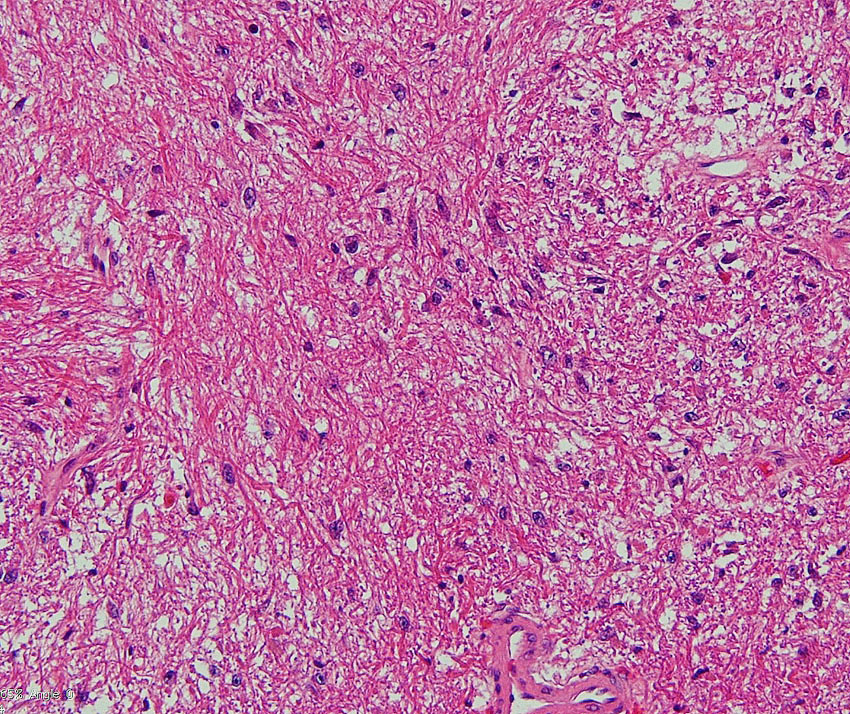

思春期のまだ増大している毛様細胞性星細胞腫

17歳です。間質に富む疎な部分は増大傾向を示しT1ガドリニウム増強される部分です。一方で,増強されない部分では,MRIで増大傾向がなく,病理では組織がコンパクトとなり,HEでは星細胞腫グレード2のよう見えます。